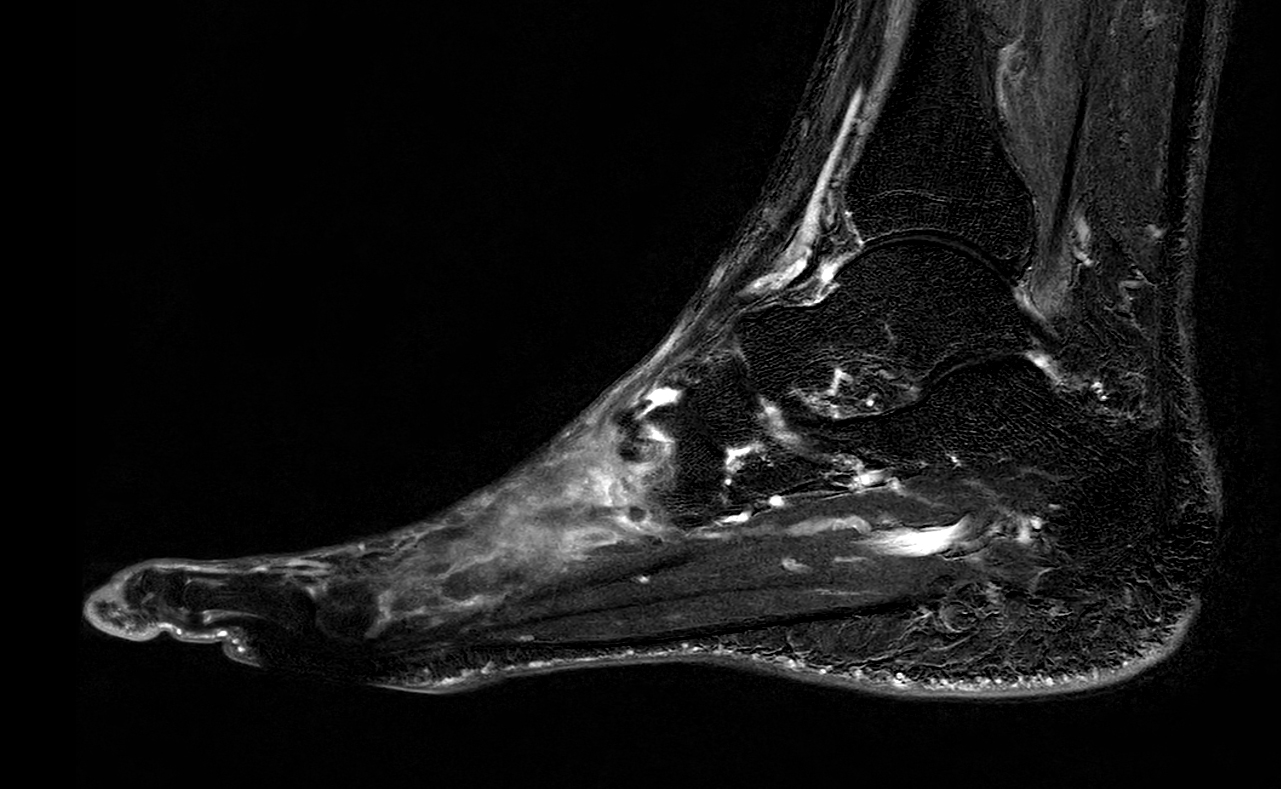

Sagittal 3D VIEW PDw SPAIR

-